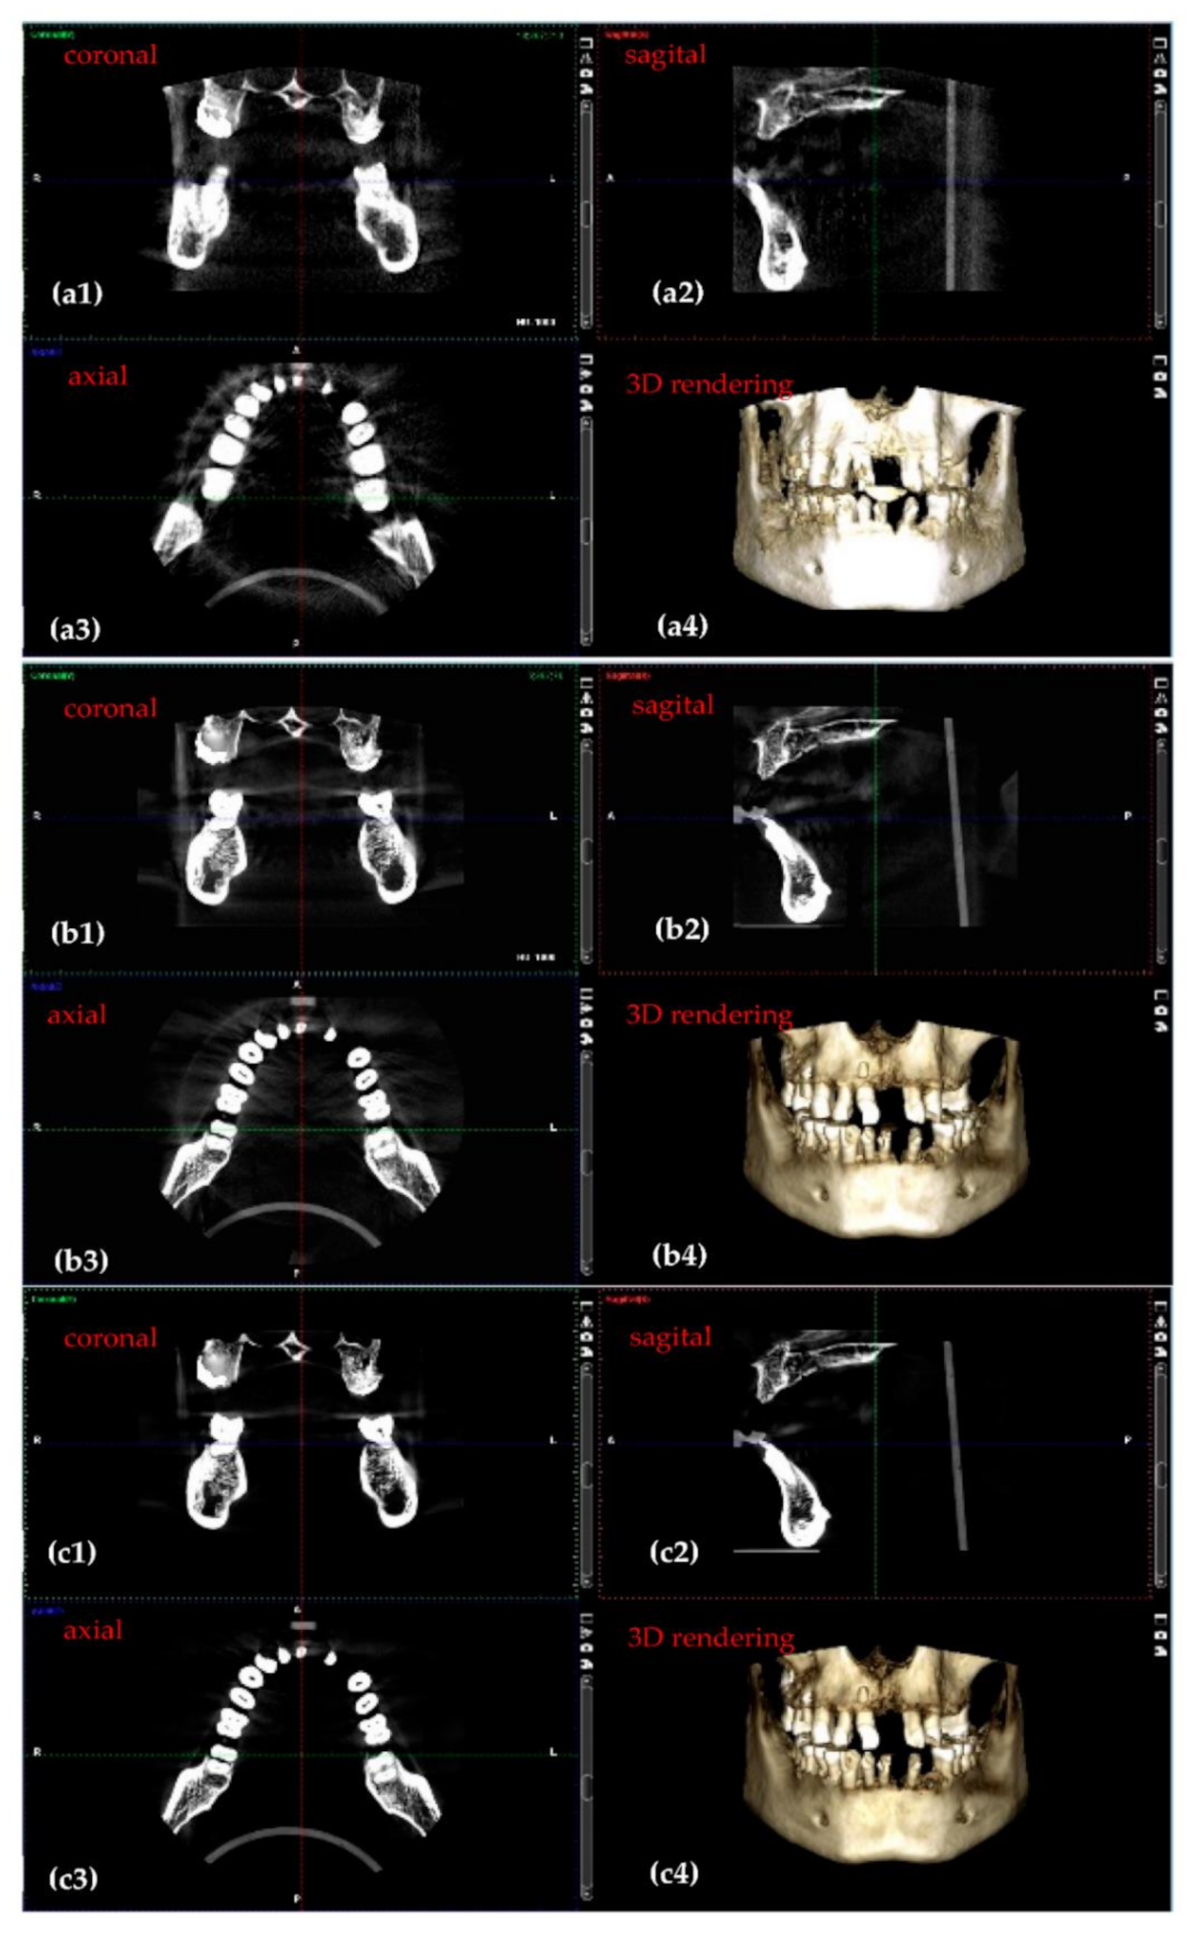

3.2. Optimized Protocol with OCT. 3D CBCT Calibration

| 3D CBCT Radiographs (Figure 9) | Anode Voltage (kV) | Current Intensity (mA) | Exposure Time (s) | Radiation Dose (µSv) |

|---|---|---|---|---|

| a | 60 | 1 | 4.95 | 1.25 |

| b | 75 | 8 | 5.09 | 25.87 |

| c | 90 | 14 | 5.08 | 86.37 |

|

3D CBCT (Figure 9) | ||||

| a | 552 | 2808 | 1680 | 0.67 |

| b | 302 | 2802 | 1552 | 0.8 |

| c | 296 | 3032 | 1664 | 0.82 |

| Diameter of Image Base (mm) | Image Height (mm) | Voxel Side (µm) | Anode Voltage (kV) | Current Intensity (mA) | Exposure Time (s) | ||

|---|---|---|---|---|---|---|---|

| Before | 80 | 200 | 84 | 14 | 12.057 | 1170 | |

| After | 80 | 150 | 90 | 14 | 5.072 | 691 |